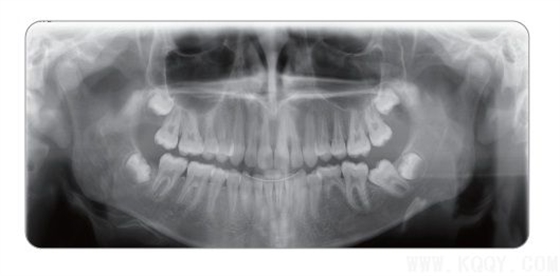

成人全景圖:顯示上下牙列、牙槽骨、神經(jīng)管及TMU,圖像均勻,前牙區(qū)結(jié)構(gòu)也可清晰顯示